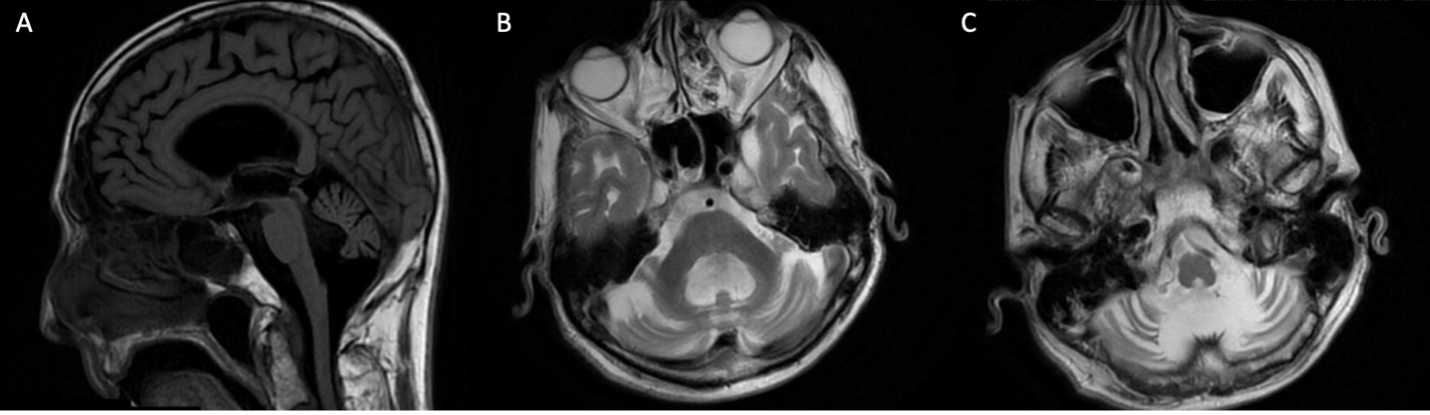

Method: A 78-year-old man, previously diagnosed with suspected MSA cerebellar type (MSA-C), presented for a second opinion after seven years of recurrent falls, progressive gait instability, impaired dexterity, orthostasis, and dysphagia. Examination revealed moderate parkinsonism, midline cerebellar features, and length-dependent sensory neuropathy. Workup revealed sensorimotor neuropathy in all extremities on EMG, a normal DaT scan, and marked cerebellar atrophy on brain MRI [Figure 1]. There was no family history of movement disorders, though his mother had frequent falls. He denied current alcohol use but previously consumed two beers per night for thirty years. A trial of carbidopa levodopa (25/100 mg up to 2 tablets TID) was ineffective. Genetic testing identified an autosomal dominant heterozygous POLG2 variant (c.404del) initially classified as a VUS. Following internal review and recommendation, the laboratory reclassified the variant as likely pathogenic, prompting amendments to past and future reports.

Figure 1